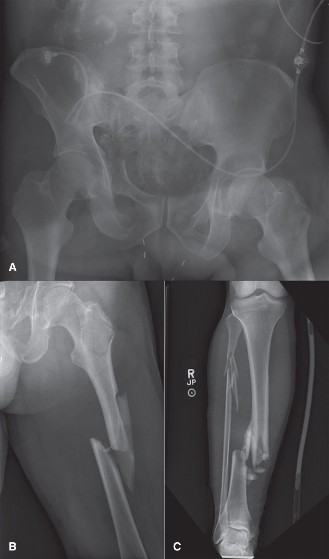

* Image:

Figure 1: Example of a unilateral external fixator construct applied to a long bone, typical of a Damage Control Orthopaedics strategy. Note the strategically placed Schanz pins and connecting bars providing immediate stabilization.